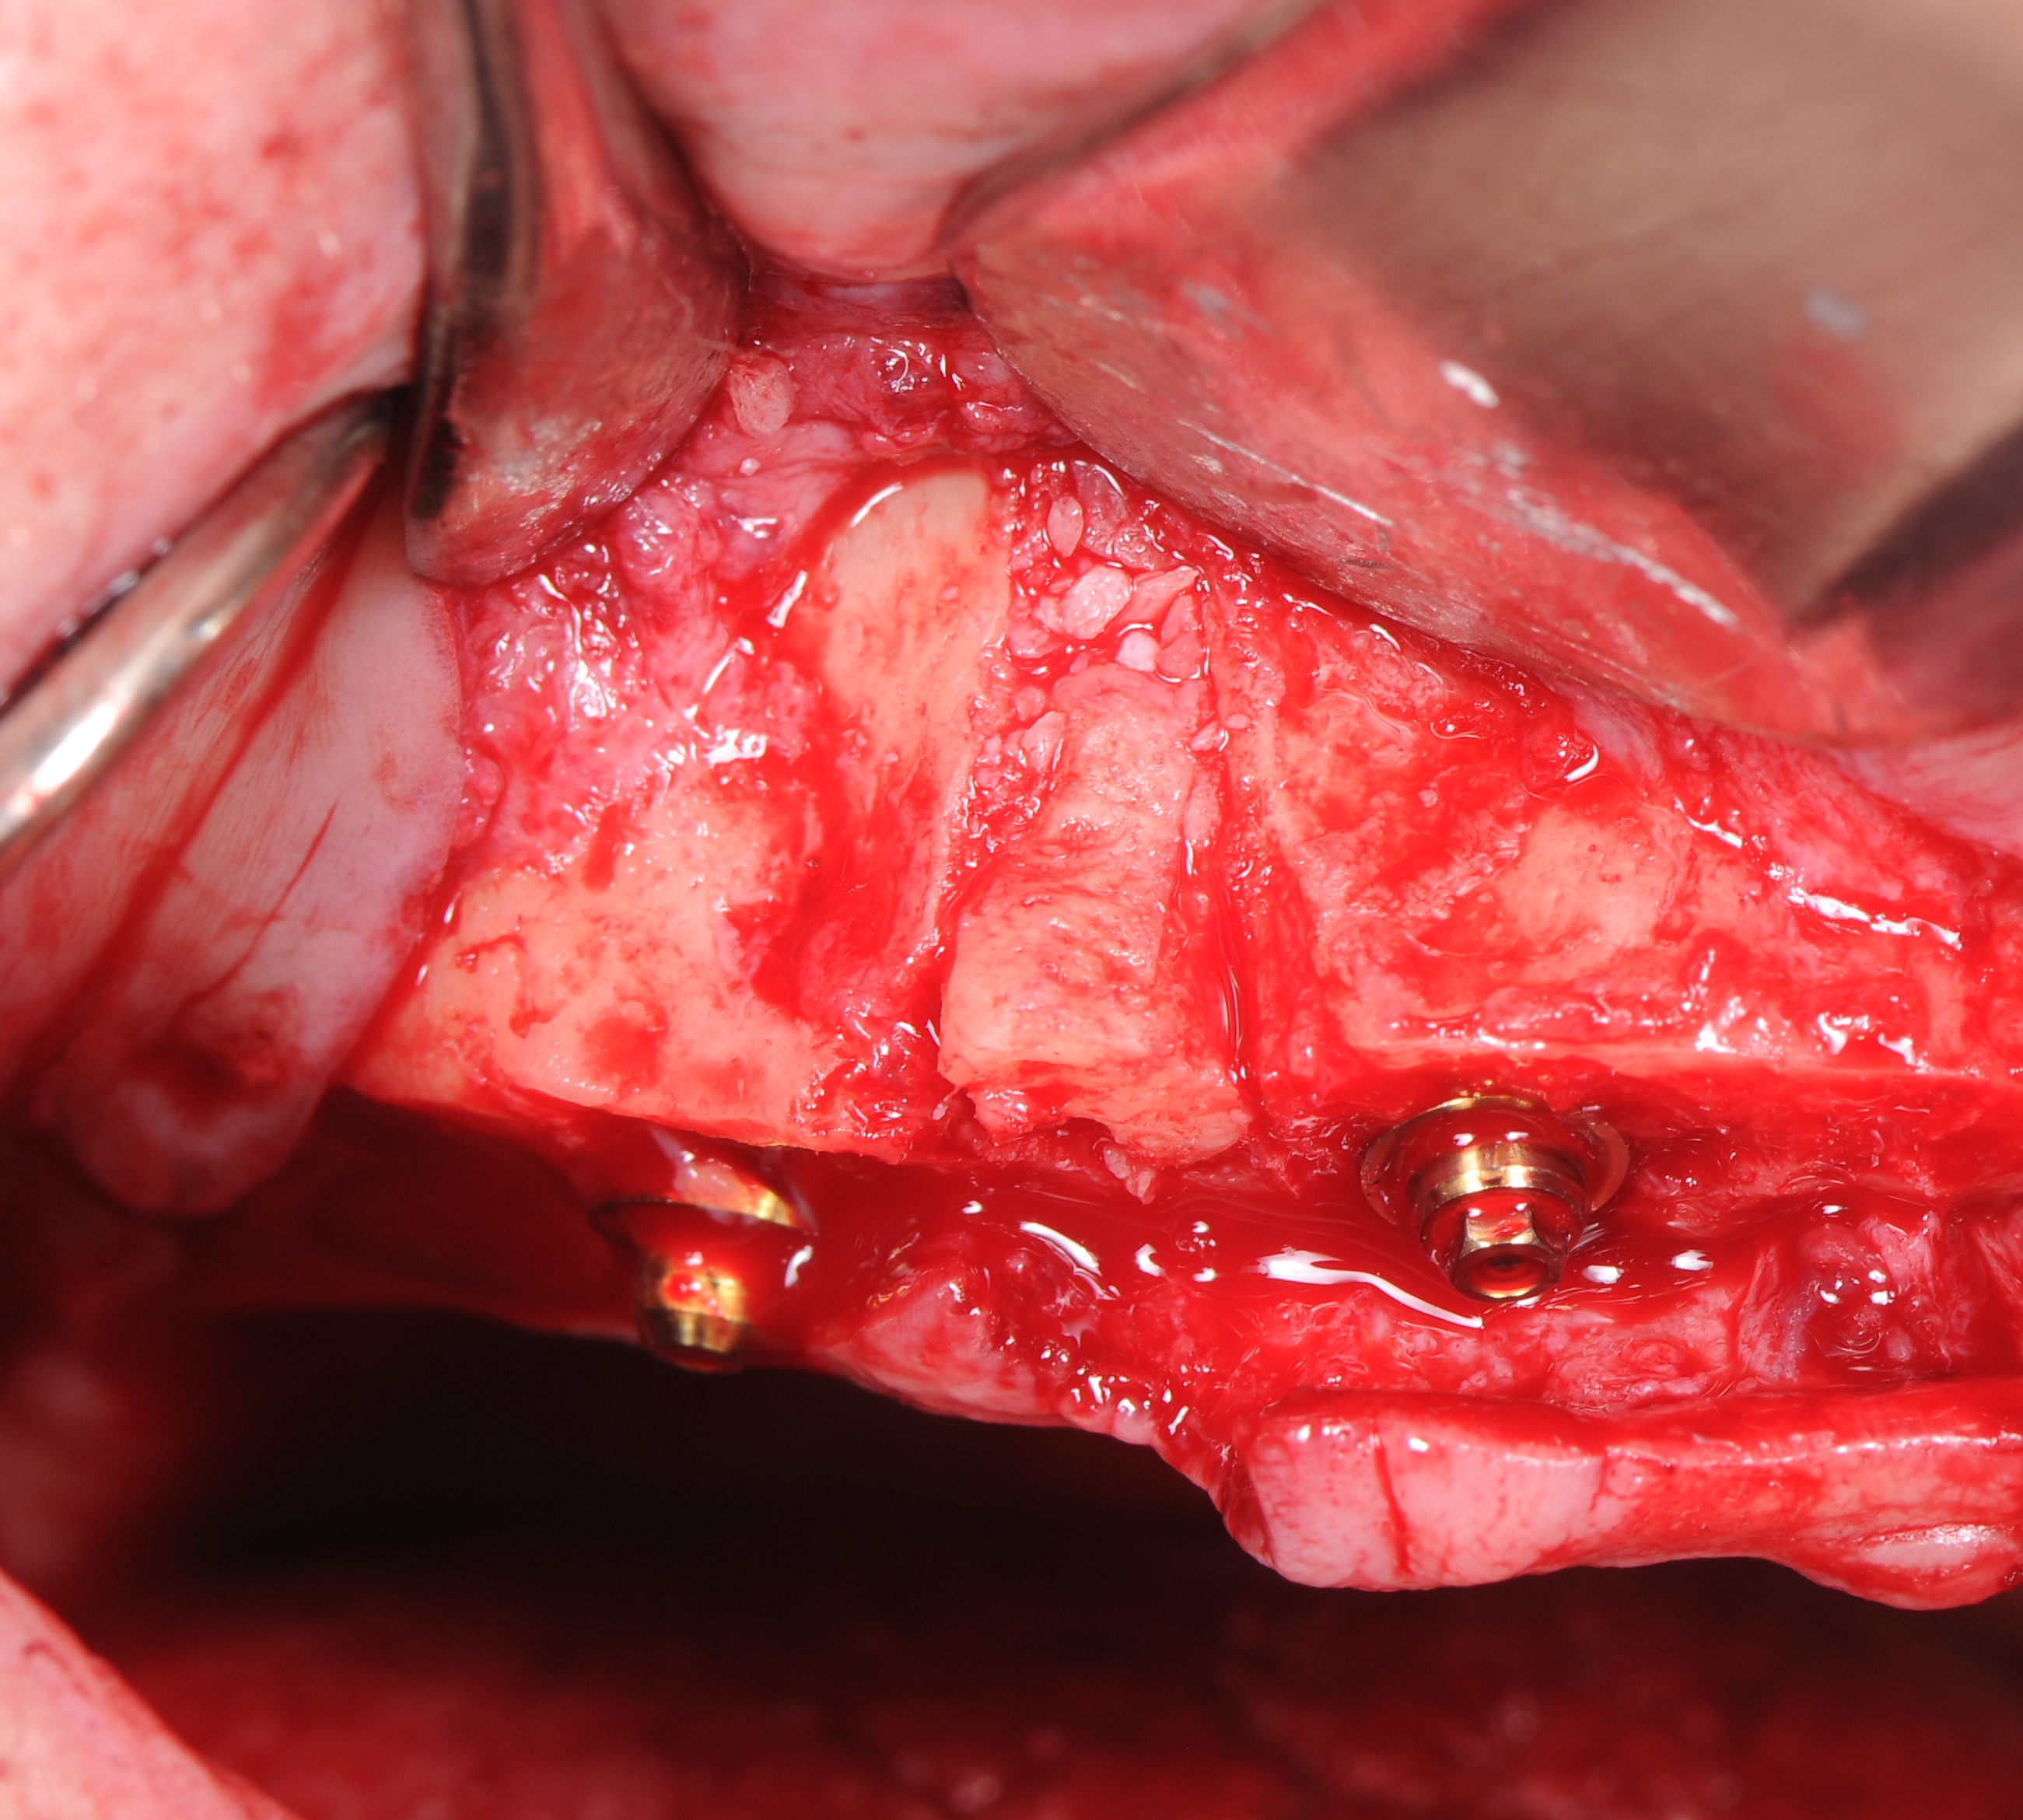

По протоколу неполного препарирования было выполнено формирование ложа для дентальных имплантатов «Nobel Parallel Conical Connection» с последующей их установкой по методике «All –on – 4». Дистальные имплантанты установлены под углом 30°, имплантаты во фронтальной зоне – вертикально(рис. 14-19). Торк (крутящий момент) всех установленных имплантатов составил более 35 N/см2 что, позволило нам одномоментно нагрузить все установленные имплантаты с установкой временного условно-съёмного протеза из акриловой пластмассы с титановым каркасом.

На имплантаты были установлены абатменты для винтовой фиксации «Multi – unit»: в боковых участках угловые 30О абатменты , во фронтальных участках – прямые абатменты (рис. 20,21)

Лунка удаленного 1.3 зуба аугментирована костным фрагментом полученном при редукции альвеолярного гребня. Его клиновидная форма позволила провести фиксацию в лунке без использования дополнительных материалов: титановых винтов или пластин. Поднутрения в окружности костного фрагмента были заполнены костно-пластическим материалом «OsteoBiol ® mp3». Области «Multi – unit» абатментов и зоны костной аугментации дополнительно изолированы коллагеновыми мембранами Creos Xenoprotect. (рис. 22-25).